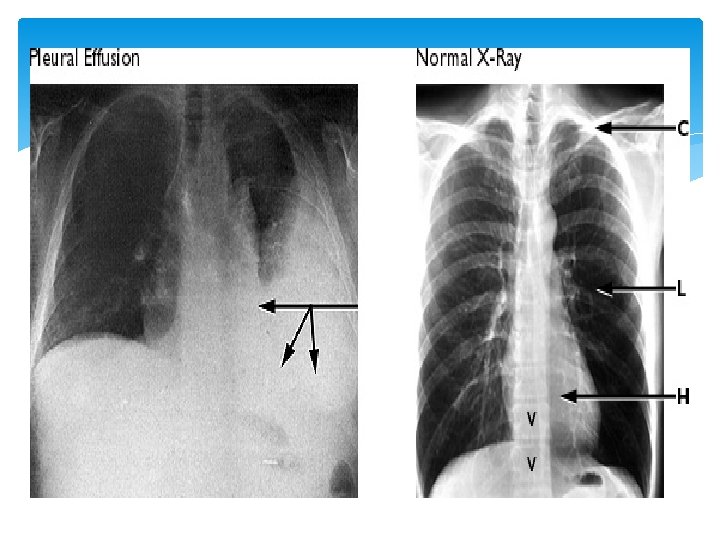

Pleural Effusion Pleural = Pleural Cavity Effusion = abnormal, excessive collection of this fluid

Pleural Effusion Abnormal buildup of fluid between linings of the lung and chest wall result of a disease process or inflammation Normally 5 to 10 m. L of serous fluid in the visceral and parietal pleura. Any more can cause great changes in intrathoracic pressure.

Signs and Symptoms Pleural effusion in itself does not cause symptoms. If effusion expands and presses on lung, patient may develop sharp, localized pain that worsens with coughing, or deep breathing. Dyspnea non-productive cough.

Signs and Symptoms cont. . . Early signs include decreased or bronchial breath sounds on the affected side, dullness to percussion, and decreased fremitus over area of fluid accumulation Auscultation: EGOPHONY Hear “A” over fluid accumulation when patient speaks “E”.